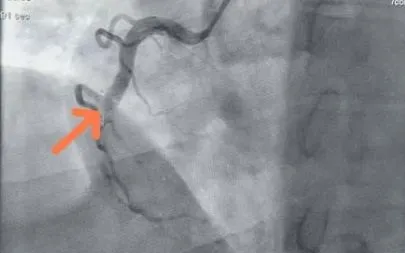

Sau xử trí ban đầu, bệnh nhân được hội chẩn trực tuyến với Bệnh viện Đa khoa tỉnh Quảng Ninh. Kết quả chụp mạch vành phát hiện tắc hoàn toàn đoạn 2 động mạch vành phải. Ekip can thiệp đã kịp thời đặt stent tái thông dòng chảy, giúp bệnh nhân qua cơn nguy kịch. Hiện sức khỏe đã ổn định.